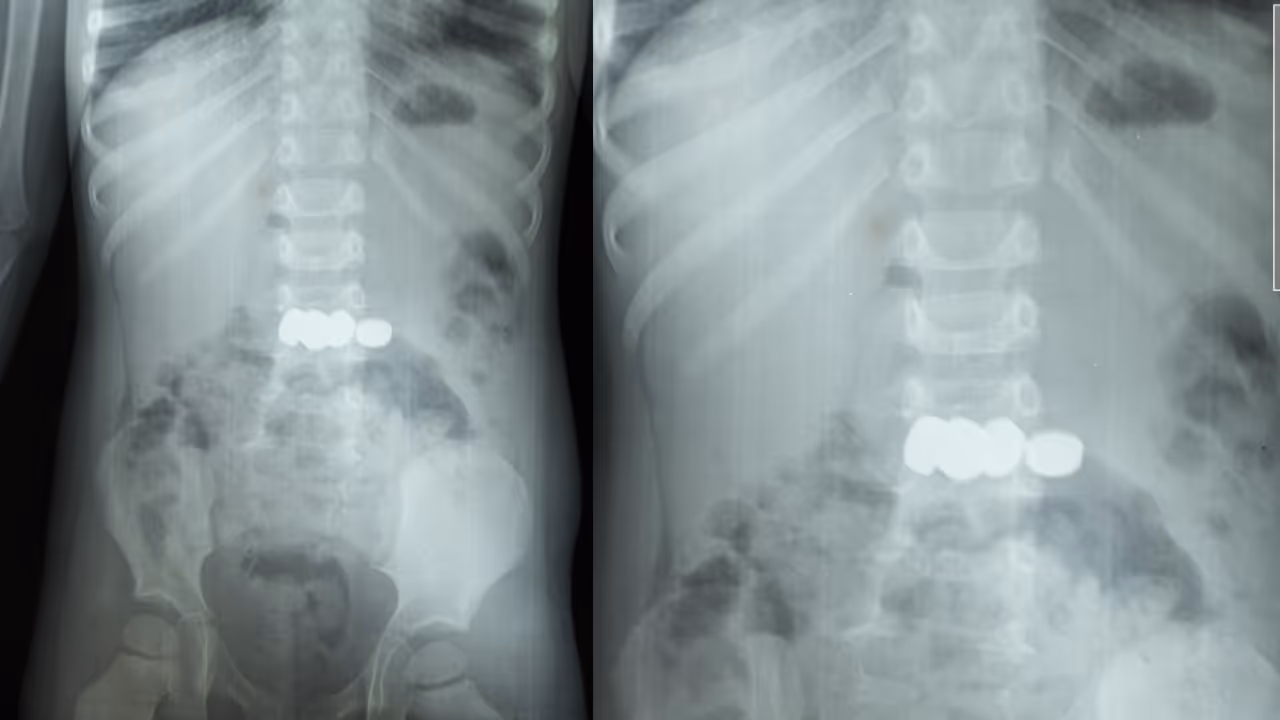

മേപ്പാടി: കളിക്കുന്നതിനിടെ അബദ്ധത്തിൽ അഞ്ച് ബാറ്ററികൾ വിഴുങ്ങിയ രണ്ട് വയസ്സുകാരന് ഡോ. മൂപ്പൻസ് മെഡിക്കൽ കോളേജിൽ നടത്തിയ അടിയന്തര എൻഡോസ്കോപ്പിയിലൂടെ പുനർജന്മം. ബത്തേരി മൂലങ്കാവ് സ്വദേശികളായ ദമ്പതികളുടെ മകനാണ് കളിപ്പാട്ടത്തിലെ ബാറ്ററികൾ വിഴുങ്ങിയത്. ഡോക്ടർമാരുടെ കൃത്യസമയത്തുള്ള ഇടപെടൽ മൂലം വലിയൊരു അപകടം ഒഴിവാക്കാനായി.

കുട്ടി ബാറ്ററികൾ വായിലിടുന്നത് ശ്രദ്ധയിൽപ്പെട്ട വീട്ടുകാർ ഒട്ടും വൈകാതെ തന്നെ കുട്ടിയെ മെഡിക്കൽ കോളേജിലെത്തിച്ചു. ഗാസ്ട്രോ എന്ററോളജി വിഭാഗം സ്പെഷ്യലിസ്റ്റ് ഡോ. സൂര്യനാരായണന്റെ നേതൃത്വത്തിലാണ് ബാറ്ററികൾ പുറത്തെടുക്കാനുള്ള നടപടികൾ ആരംഭിച്ചത്. എൻഡോസ്കോപ്പിയിലൂടെ അഞ്ച് ബാറ്ററികളും സുരക്ഷിതമായി പുറത്തെടുത്തു. ഡോ. അഖിൽ, ഡോ. അഞ്ജന എന്നിവരും ഈ ദൗത്യത്തിൽ പങ്കാളികളായി.